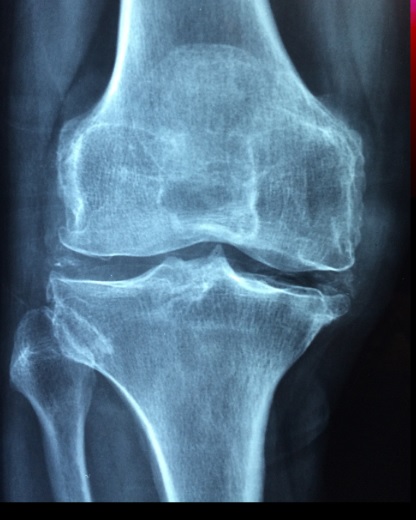

관절염은 관절에 염증과 통증을 일으키는 조건들을 설명하기 위해 사용되는 용어입니다. 관절염에는 많은 다른 종류가 있고, 각각의 원인은 다양할 수 있습니다.

1. 나이가 들면서 관절을 감싸주는 연골이 닳아 관절염으로 이어질 수 있습니다.

3. 부상입니다. 관절에 대한 외상은 나중에 관절염으로 이어질 수 있습니다.